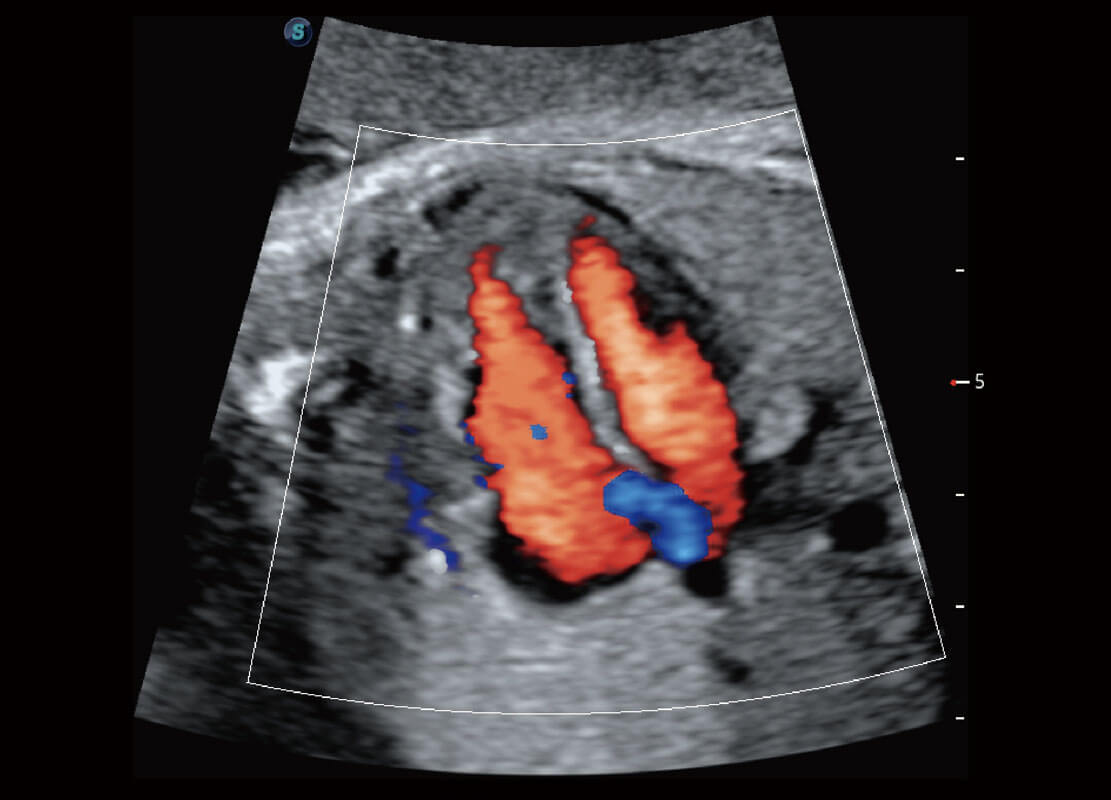

胎心筛查

P60搭载一系列胎儿心脏成像技术,实现精细的胎儿心脏评估。

• 四腔切面

• 四腔心血流

• 右室双出口

• 胎心容积成像